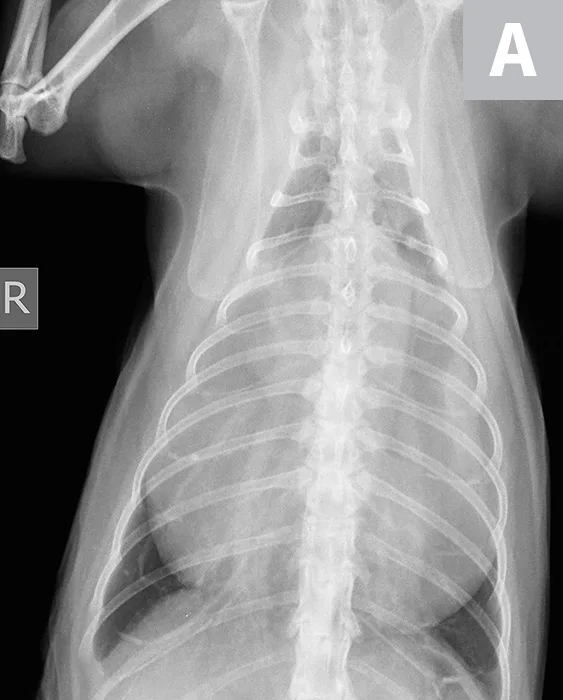

Two-view thoracic radiographs (Figure 1) were obtained with Joker under mild sedation (butorphanol [0.2 mg/kg IV]). Marked widening of the cardiac silhouette, both in height and width, with loss of delineation of the caudal cardiac margin, was observed. Superimposition of air tubular opacities to the cardiac silhouette were also noted. The liver was not visible at its physiologic position in the cranial abdomen. Considering these radiographic findings, a presumptive diagnosis of peritoneopericardial diaphragmatic hernia (PPDH) was made.

Ventrodorsal (A) and lateral (B) thoracic radiographs demonstrating an enlarged cardiac silhouette (arrowheads) with gas-filled tubular opacities consistent with the GI tract (asterisks) and loss of the caudal cardiac margin (arrows)